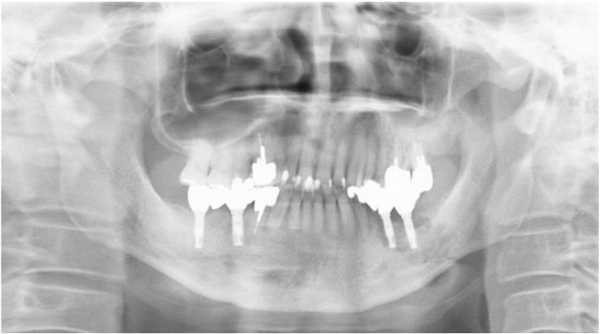

На ортопантомограмме контурировалась слабо демаркационная зона деструкции костной ткани в области имплантатов на месте 35 и 36 зубов, при этом поражение достигало нижнего края челюсти, что в результате спровоцировало возникновение патологического перелома. Вокруг имплантатов с правой стороны челюсти никаких патологических поражений отмечено не было (фото 2). С помощью КТ-сканирования удалось подтвердить деструкцию нижней челюсти слева и наличие линии перелома через всю толщу костной ткани (фото 3).

Фото 2. Ортопантомограмма пациента до лечения.

Фото 3. КТ-изображения нижней челюсти с левой стороны: а) аксиальный срез в области левого первого моляра; b) корональный срез в области левого первого моляра.